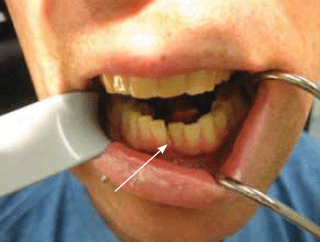

Post-traumatic malocclusion is often reported by the patient and should generally be visible by intra-oral inspection. Test occlusion by asking the patient to close their mouth to identify any malalignment of the teeth. A step in the occlusal plane with a ruptured gingiva at the site (Figure 1) or a sublingual haematoma (Figure 2) are strong indicators of mandibular fracture.8

Figure 1. A step in the occlusal plane and ruptured

gingival (arrow) associated with a mandibular fracture

Figure 1. A step in the occlusal plane and ruptured gingival (arrow) associated with a mandibular fracture

Figure 2. A sublingual haematoma (arrow) can be an

indicator of a mandibular fracture

Figure 2. A sublingual haematoma (arrow) can be an indicator of a mandibular fracture